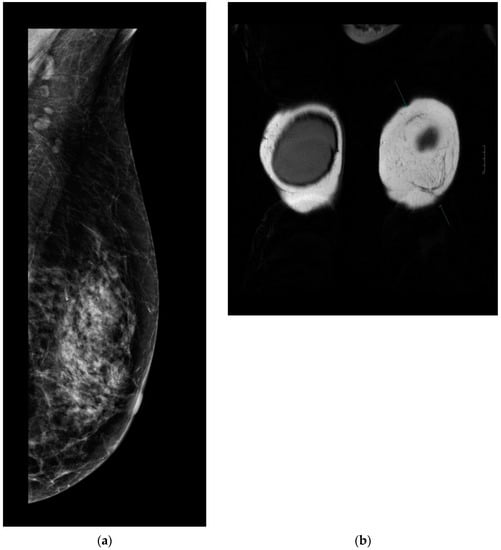

Every patient underwent control complex breast imaging (mammography as well as breast and axillary US) according to the ESMO guidelines for treatment and follow-up. Breast MRI was performed in 32 patients: 17 in the MG and 15 in the NMG. According to the control breast imaging examinations, the mesh did not disturb the clear visualization or oncological control of the underlying parenchyma (Figure 4a,b).

Figure 4.

(a). Follow-up mammography after ULTRAPRO sling mastopexy. The mesh is not visible on the mammography images; therefore, it does not influence the oncological surveillance. (b). Arrows show the mesh on contrast-enhanced MRI. The mesh appears clearly/well depicted on the MR (coronal T2 weighted) images without disturbing the evaluation of the parenchyma.

After 12 months, there were no signs of chronic seroma formation or any other visualization disturbing the lesion on the symmetrization side if the mesh was used.